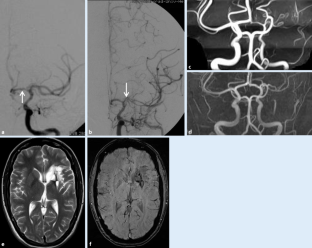

Abb. 4